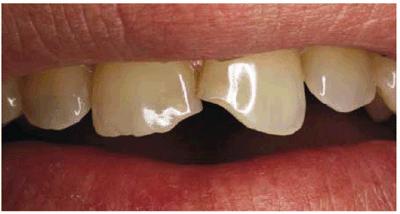

this condition is seen in a patient who fractured a tooth (Figur 323s1823d e 18-5A). During the clinical examination,

this patient expressed his desire for a younger and brighter smile. The teeth

were then prepared, and an impression was made for six porcelain laminate

veneers. To help protect the occlusion, porcelain was wrapped incisally to the

lingual surface (Figur 323s1823d e 18-5B). What began as an emergency visit

to repair a fractured tooth resulted in enhancing this patient's entire smile (Figur 323s1823d e 18-5C

Figur 323s1823d e 18-5A: This 65-year-old man had fractured his right central incisor. Because he desired a younger and brighter looking smile, six porcelain laminates were treatment planned.

Figur 323s1823d e 18-5B: This patient had an end-to-end bite, which required additional incisal edge reinforcement.

Figur 323s1823d e 18-5C: Note the improvement in this man's smile with a lighter shade and teeth that are more proportionate to each other.